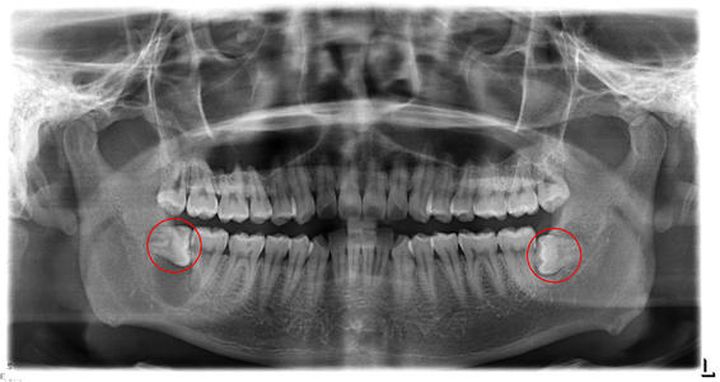

都是拔智齿,为什么术后反应差别如此巨大呢?主要有两方面的因素,其一是看智齿的情况,如果是自然生长没有阻生埋伏的智齿拔除后一般不会有太太反应。而如果是埋伏牙的话就比较麻烦。

拔除埋伏牙时,要先切开外层牙床并将其扒开,然后将智齿分段割开,再将被分割的智齿取出,最后缝合牙龈。其过程就相相当于一台小型手术,术后反应自然会比较严重。